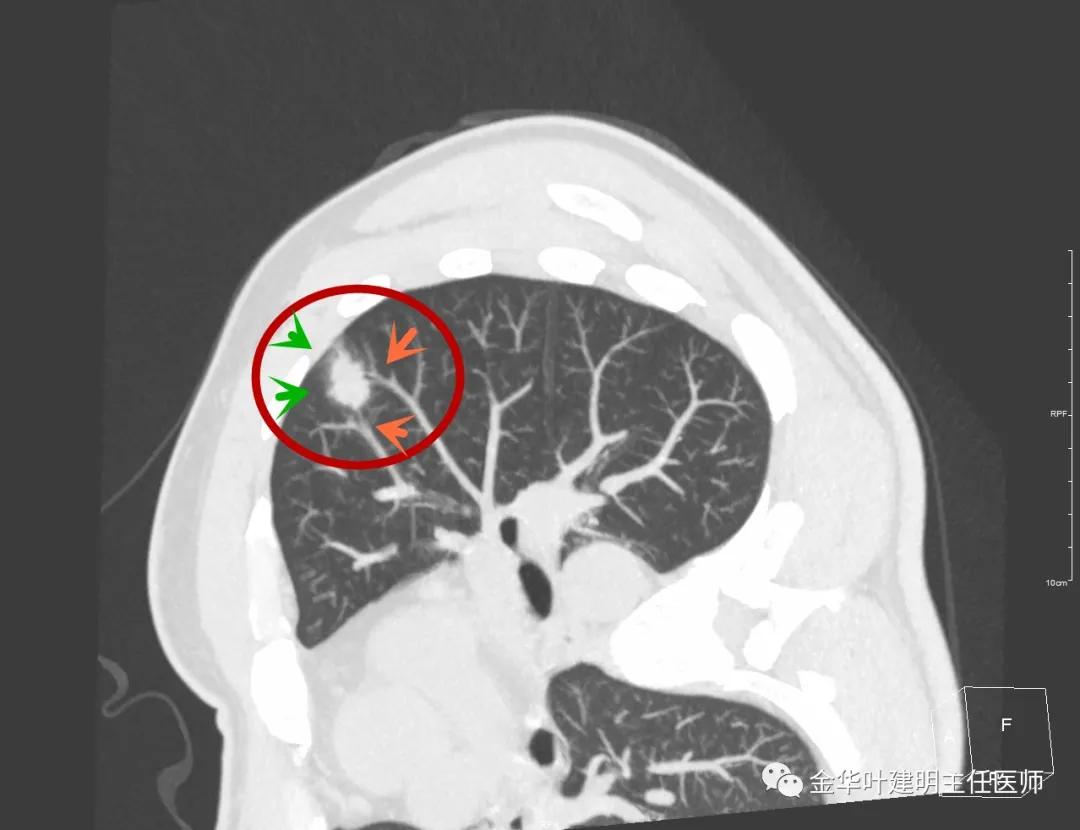

此层面相对最不舒服,病灶表面不平整。桔色箭头示血管进入病灶,但仍有绿色箭头示病灶有晕征(边缘是模糊的,不似肿瘤那种细毛刺且相对清楚轮廓)

紫色箭头示病灶的边缘向内凹陷,说明无膨胀性,绿色示晕征,粉色箭头指向病灶

此层面示病灶呈三角形,缺乏膨胀性,边缘较直,没有毛刺征,实性部分没有收缩纠集感,绿色箭头示晕征